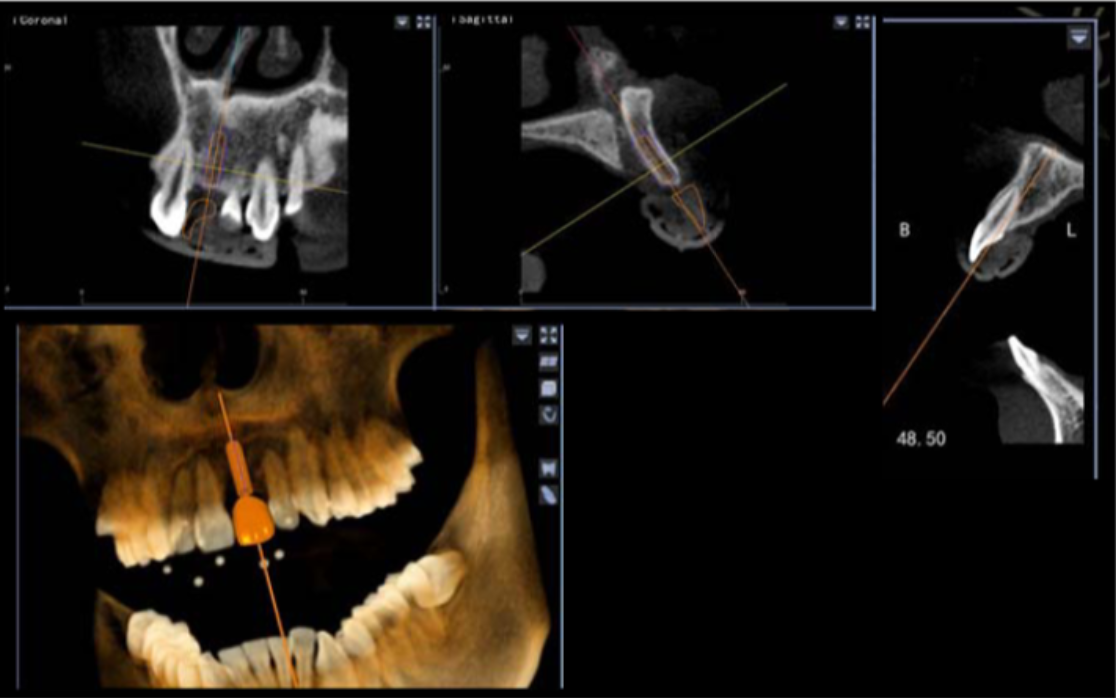

避免骨劈開(kāi)及切牙管,這是由華西口腔的楊醒眉教授主刀的一次完美的前牙美學(xué)區(qū)數(shù)字化種植手術(shù)的病例!

此病例中主刀醫(yī)生借助迪凱爾數(shù)字化口腔種植手術(shù)導(dǎo)航系統(tǒng),精確的控制每鉆的定點(diǎn)精度和角度,保證了每次制備定點(diǎn)誤差小于0.4mm,角度偏差不大于3.5°,極大的保證了種植體按照種植前的手術(shù)設(shè)計(jì)就位。